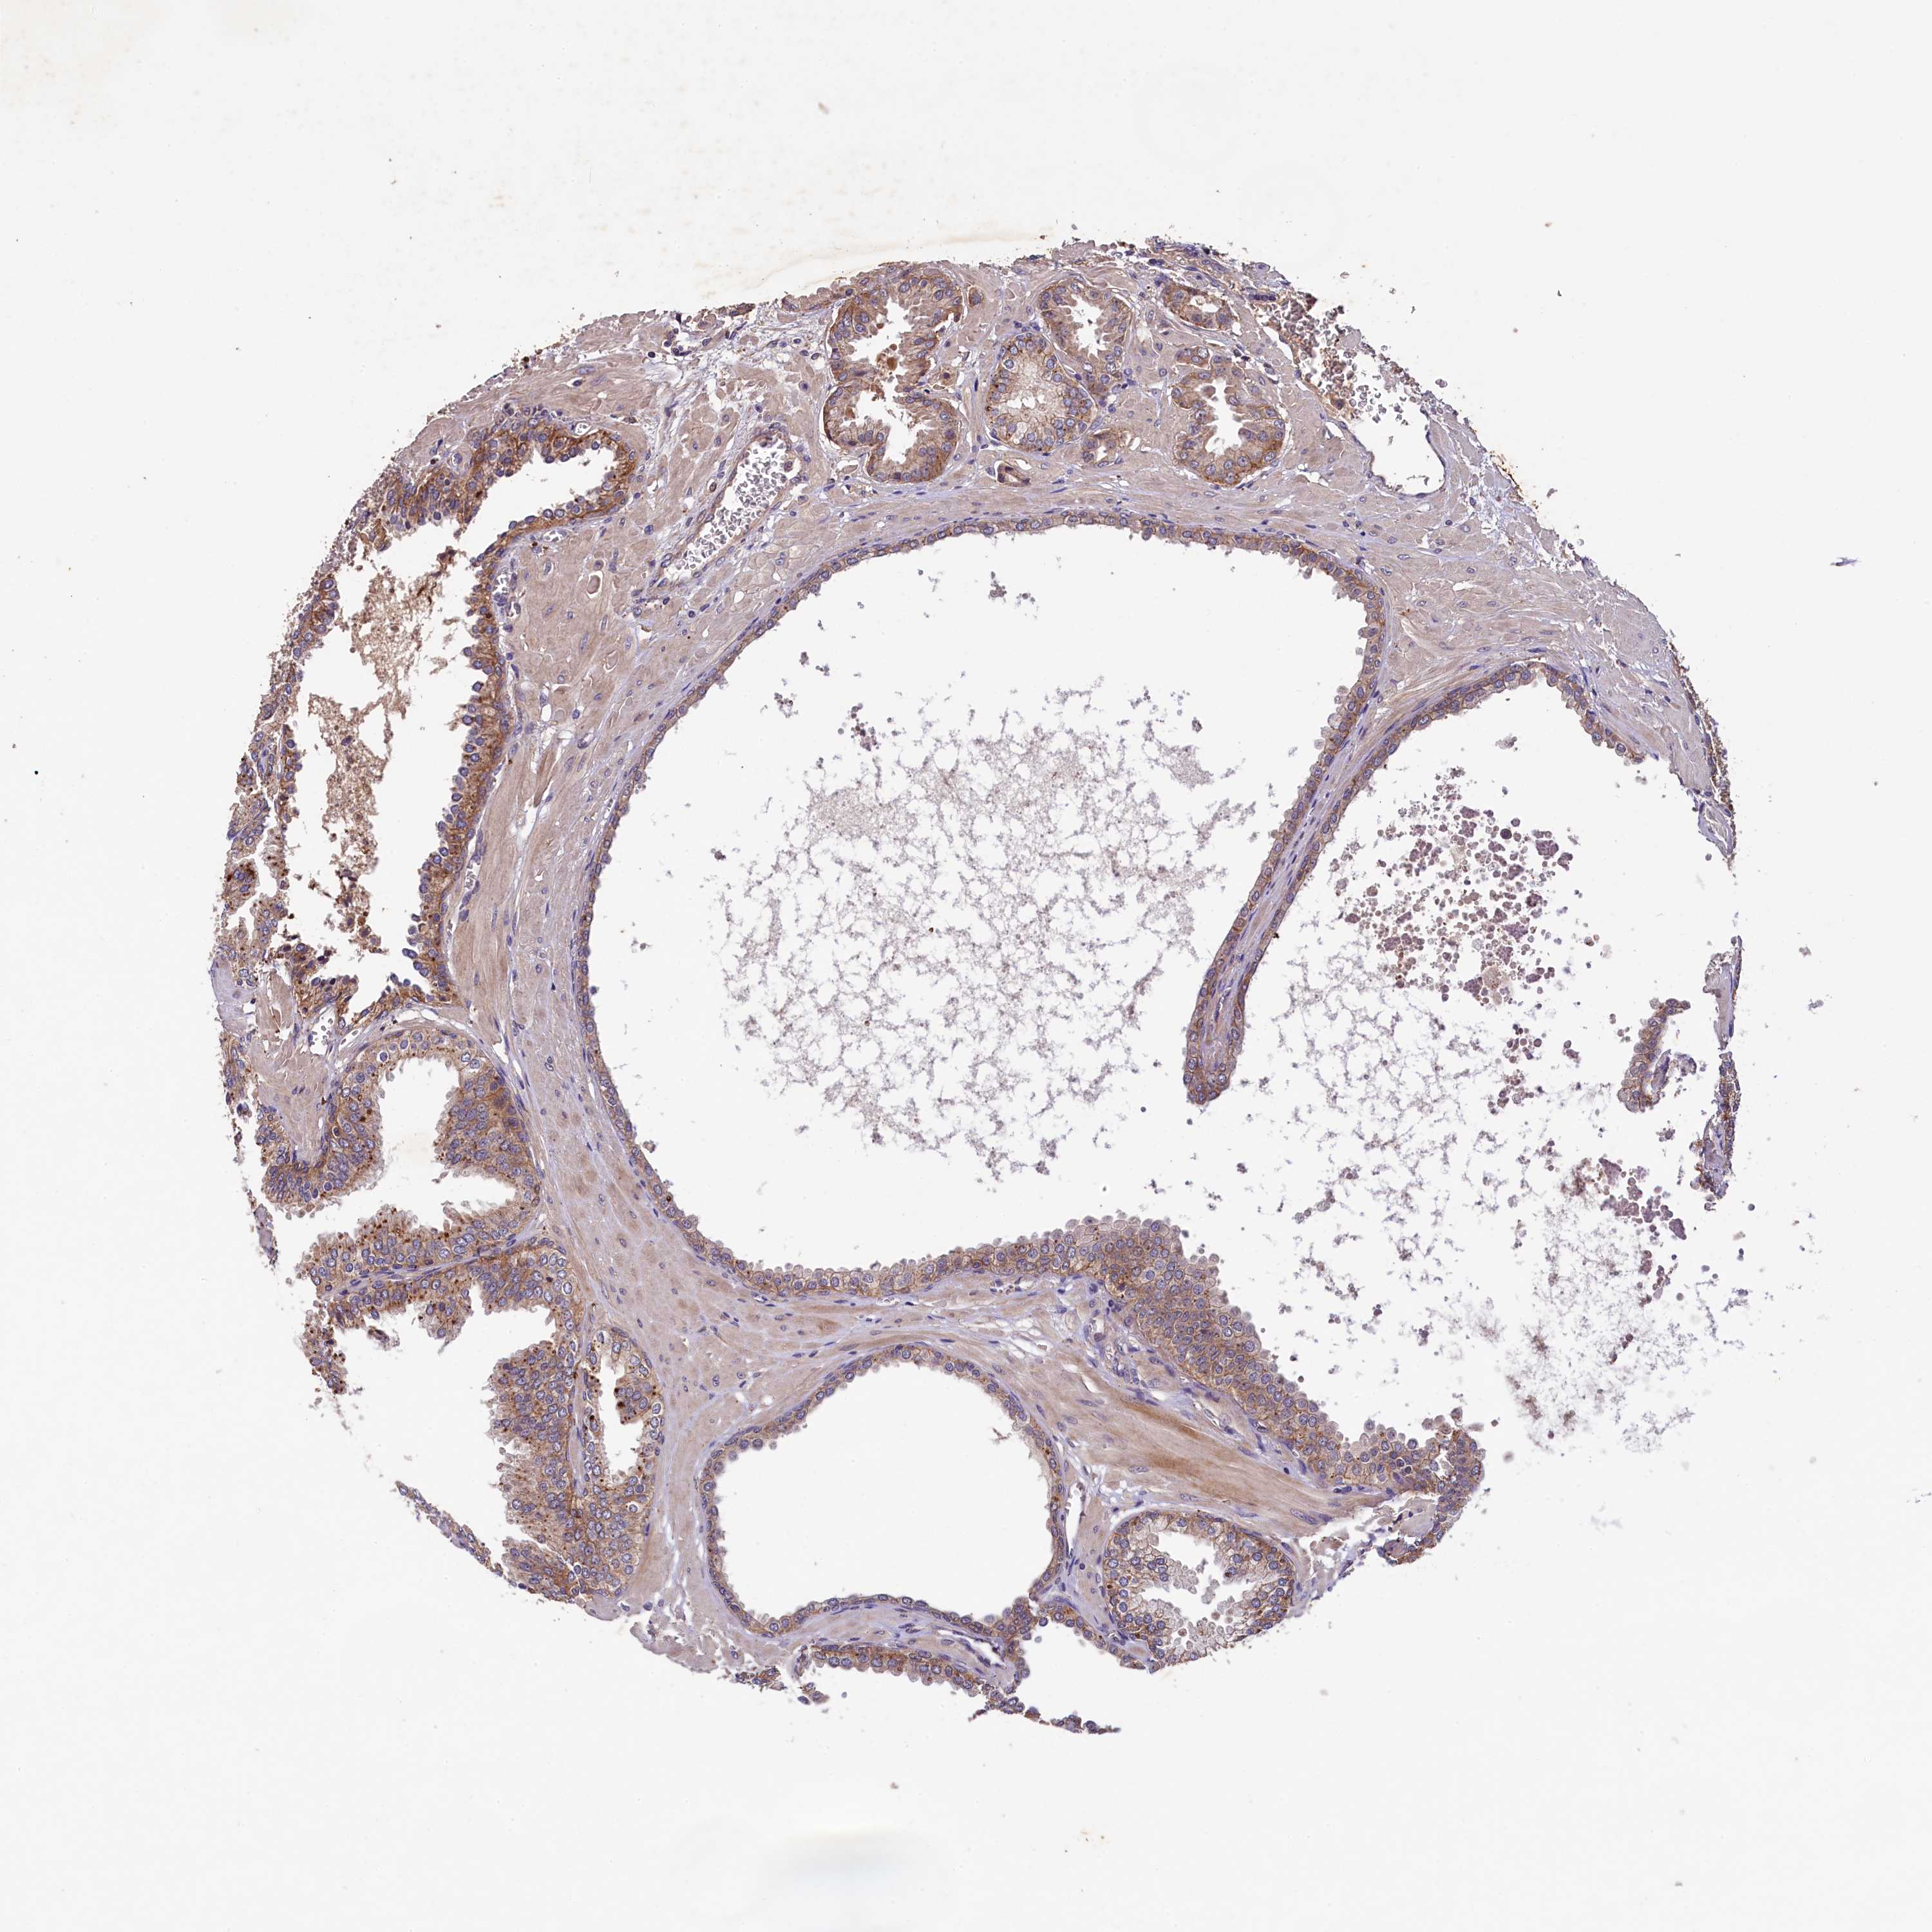

PROSTATE CANCER - Protein expressioni

A mouse-over function shows sample information and annotation data. Click on an image to view it in a full screen mode. Samples can be filtered based on level of antibody staining by selecting one or several of the following categories: high, medium, low and not detected. The assay and annotation is described here.

Antibody stainingi

Antibody staining in the annotated cell types in the current human tissue is reported as not detected, low, medium, or high, based on conventional immunohistochemistry profiling in selected tissues. This score is based on the combination of the staining intensity and fraction of stained cells.

Each image is clickable and will lead to virtual microscopy that enables deeper exploration of all samples and also displays staining intensity scores, fraction scores and subcellular localization as well as patient and tissue information for each sample.

Antibody HPA040586

Staining

High

Medium

Low

Not detected

Intensity

Strong

Moderate

Weak

Negative

Quantity

>75%

75%-25%

<25%

None

Location

Nuclear

Cytoplasmic/membranous

Cytoplasmic/membranous,nuclear

Adenocarcinoma, NOS

Adenocarcinoma, High grade

Adenocarcinoma, Low grade